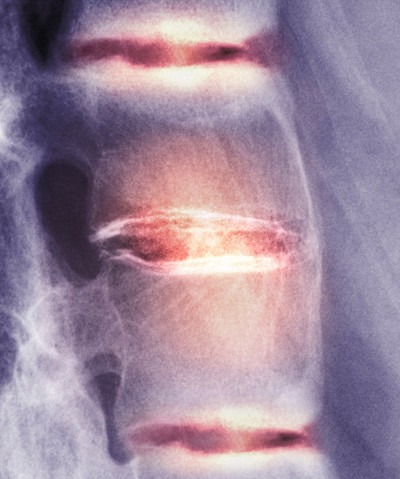

Illustrasjonsfoto: Science Photo Library